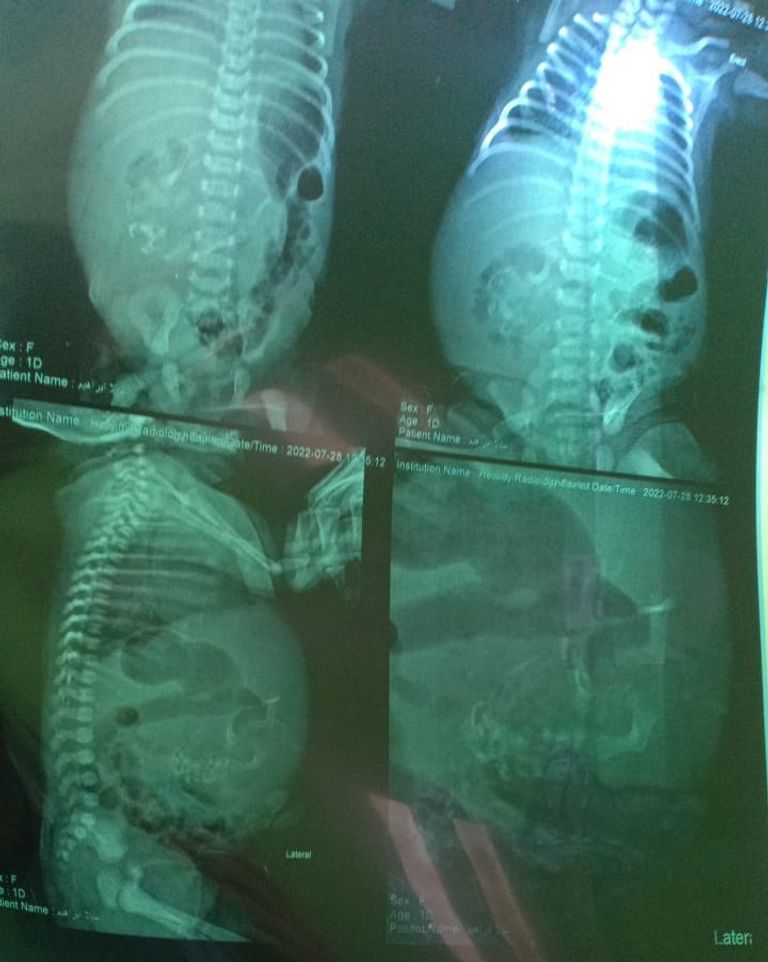

وقال الطبيب المصري، في تصريحات لـ"العين الإخبارية"، إن الطفلة المولودة حديثًا خضعت لجميع الفحوصات الطبية والأشعة المقطعية تمهيدًا لاستئصال الجنين.

وقال الدكتور زياد إسماعيل في تصريحات سابقة لـ"العين الإخبارية"، إنه لاحظ انتفاخًا كبيرًا في بطن الطفلة بعد ولادتها، فأمر بإجراء الأشعة والفحوصات اللازمة لبيان الحالة.

وأضاف الطبيب المصري أن المولودة حالتها مستقرة، لكن الأشعة أظهرت وجود أنسجة تشبه الجنين غير المكتمل داخل بطنها، مشيرا إلى أن هذه الحالة هي الثانية من نوعها في مصر.

وأوضح الطبيب زياد إسماعيل أن هذه الحالة تسمى "جنين داخل جنين"، وهي عبارة عن خلل جيني يؤدي إلى تكون جنين آخر في الرحم ودخوله في جسم الجنين الأول المكتمل.